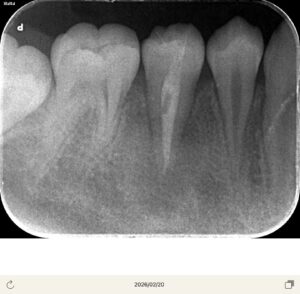

患者さんは10代の男性

歯茎がかなり腫れてきた。痛みが続く

ところが7ヶ月経過して急に歯茎が腫れてきたとのことで来院

ここの真ん中の歯に中心結節があったが、そこの破折からの根管内への細菌感染とすぐに判断した。CBCTを撮影させていただき、歯根は完成しているため、再生歯内療法(REP)ではなく、MTAで根管充填をしようと計画

当日根管治療を実施し、根管充填まで行なった